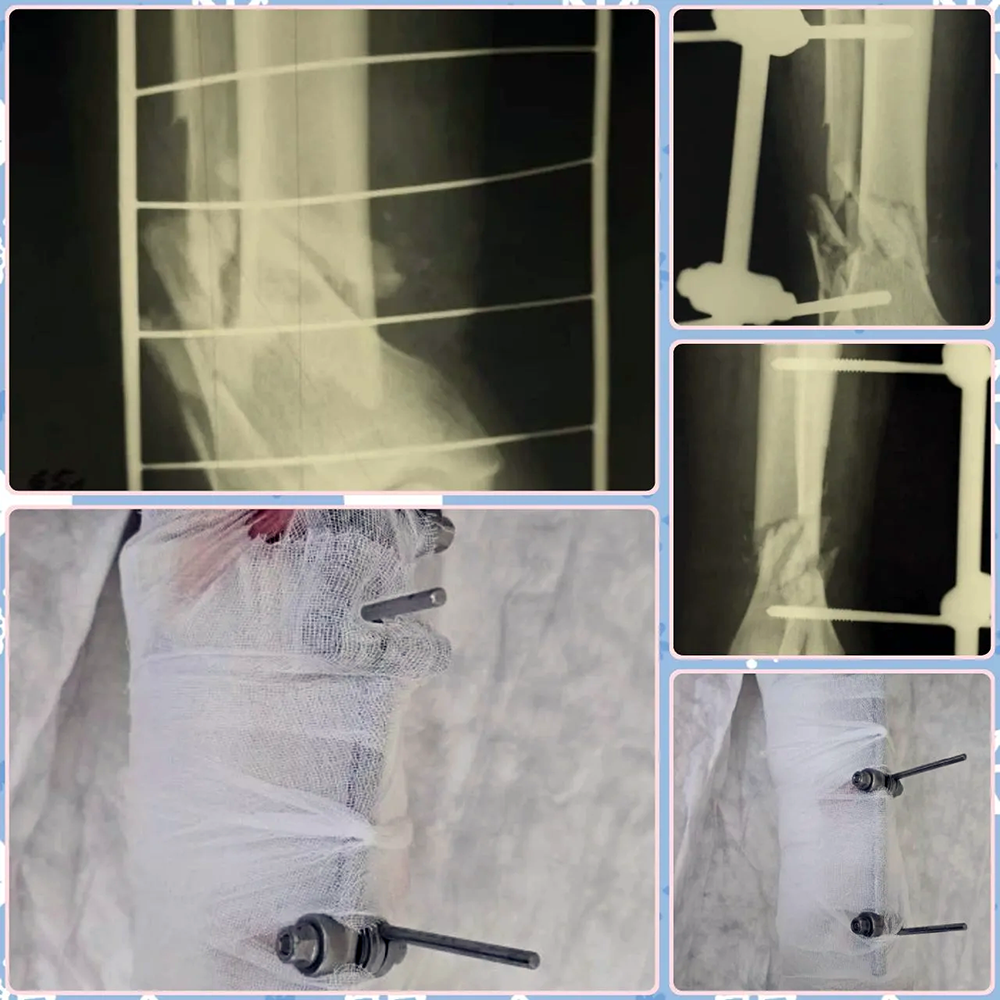

Как сообщает пресс-служба БГКБ, антигероем этого периода становится угловая шлифовальная машина – «болгарка». Только за одно дежурство в отделение поступает по 1–2 человека с чудовищными травмами кисти.

«Люди, стремясь сэкономить время, совершают смертельную ошибку: снимают защитный кожух и ставят циркулярный диск по дереву, – предупреждает Алексей Засенцев. – Когда диск закусывает, инструмент отбрасывает, и происходит полное пересечение сосудов, нервов и костей. Палец оказывается в пакетике, но восстановить тонкую функцию кисти после рваной раны практически невозможно».